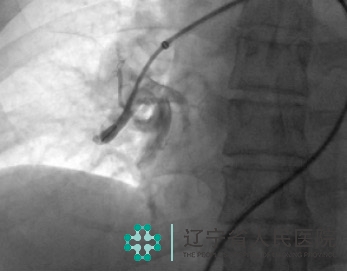

70岁的李阿姨反复出现胸闷、气短,日常需要靠轮椅出行。辗转多家医院治疗,效果不佳。来到我院,经过肺动脉CTA及超声心动图检查,确诊为“慢性血栓栓塞性肺动脉高压”,超声心动图提示重度肺动脉高压,右心室显著增大,收缩功能差,双肺部血管血流灌注缺损,病情非常严重。

经过慎重的术前评估,我们为其实施了经皮肺动脉球囊成形术,术中寻找到了严重狭窄甚至闭塞的肺动脉,进行有效球囊扩张。术后,患者活动耐量明显改善,胸闷、憋气症状得到缓解。

肺动脉球囊成形术的机理是通过肺血管小球囊扩张的方式改善阻塞血管的血流,达到重建肺循环的目的,对于无法耐受开胸手术的患者非常适用,治疗后,患者活动耐量可明显提高,部分患者可停用靶向药物。